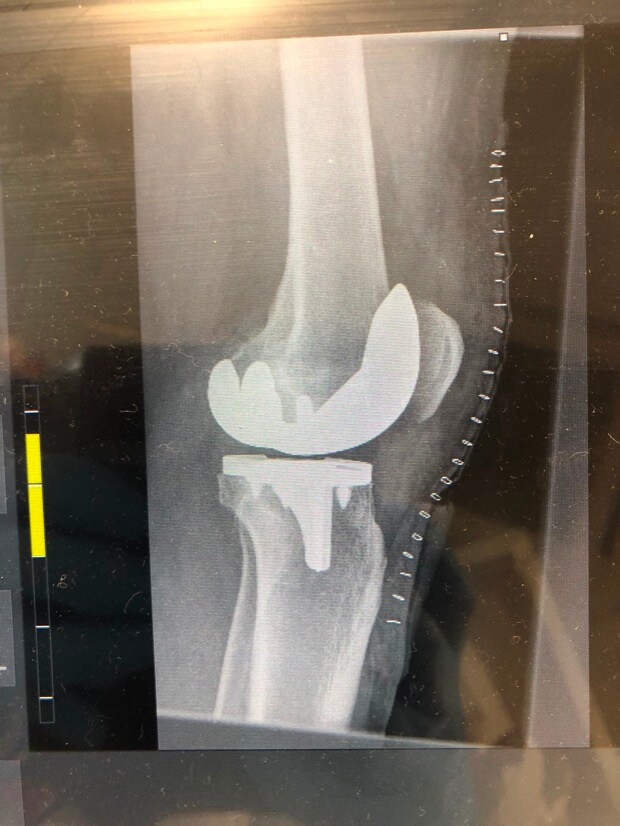

1. Evening TT’ers I’m one week into recovery from having total knee replacement surgery on my left knee. I’m wondering if anyone else out there has had the same surgery and can provide some advice on how long it took after surgery before you were back on the golf course or at least swinging a club. Are there any pitfalls I should avoid? All advice welcome including tongue in cheek to cheer me up!!! Cheers………..Steve

3. Stephen, I've been there - I've got similar X-rays, though mine have random bits of metal from earlier ACL's. Right knee for me. Right knee is "better" as the loading through the swing is more intense on the left knee for right handers. One week in can be a low point. No point in being a hero - take whatever painkillers they give you!! Stairs will be an issue for some considerable time I'm afraid. You will, however, be able to use stairs to strengthen your muscles. Be diligent about your physio and to get access to an exercise bike of some description! When allowed, I did lots of walking and found it helped. I had my op in the November and was ready for the Driving Range the following March. Some say they were back on the golf course six weeks after the op - I would consider that to be a very risky strategy. It's a major reconstruction and it takes time to heal. The numbness wears off eventually but don't expect it to be exactly like a natural knee - it's good, but it's not that good! Oh, and be prepared to be stopped by Security at every airport - You'll set of the metal detector alarms!!